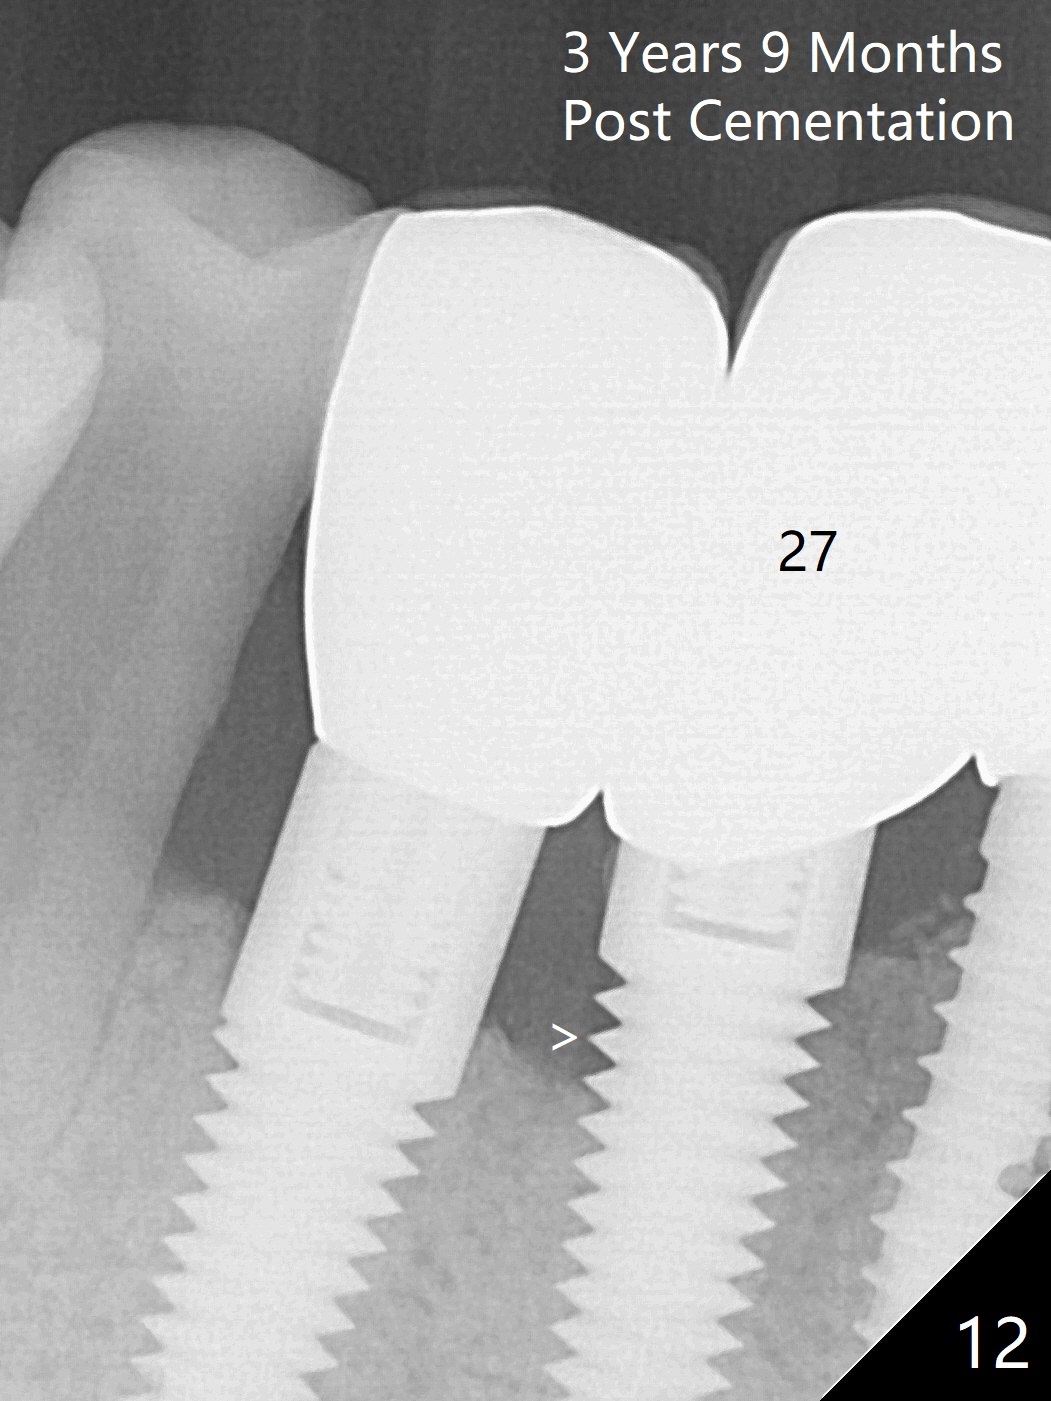

The implants remain asymptomatic years months post cementation (Fig.12), while the one at #27 is associated with buccal and lingual swelling and hemorrhage and bone loss (Fig.13).  There is bone loss distal to #27 without symptom 3 years 9 months post cementation (Fig.12).  Periimplantitis develops buccal and lingual 4 years 5 months post cementation (coronavirus, Fig.13).  Sticky bone and PRF are used after debridement.  There is no discomfort 7 days postop (Fig.14,15).